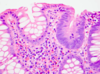

Normal Small Intestine

Normal Small Intestine